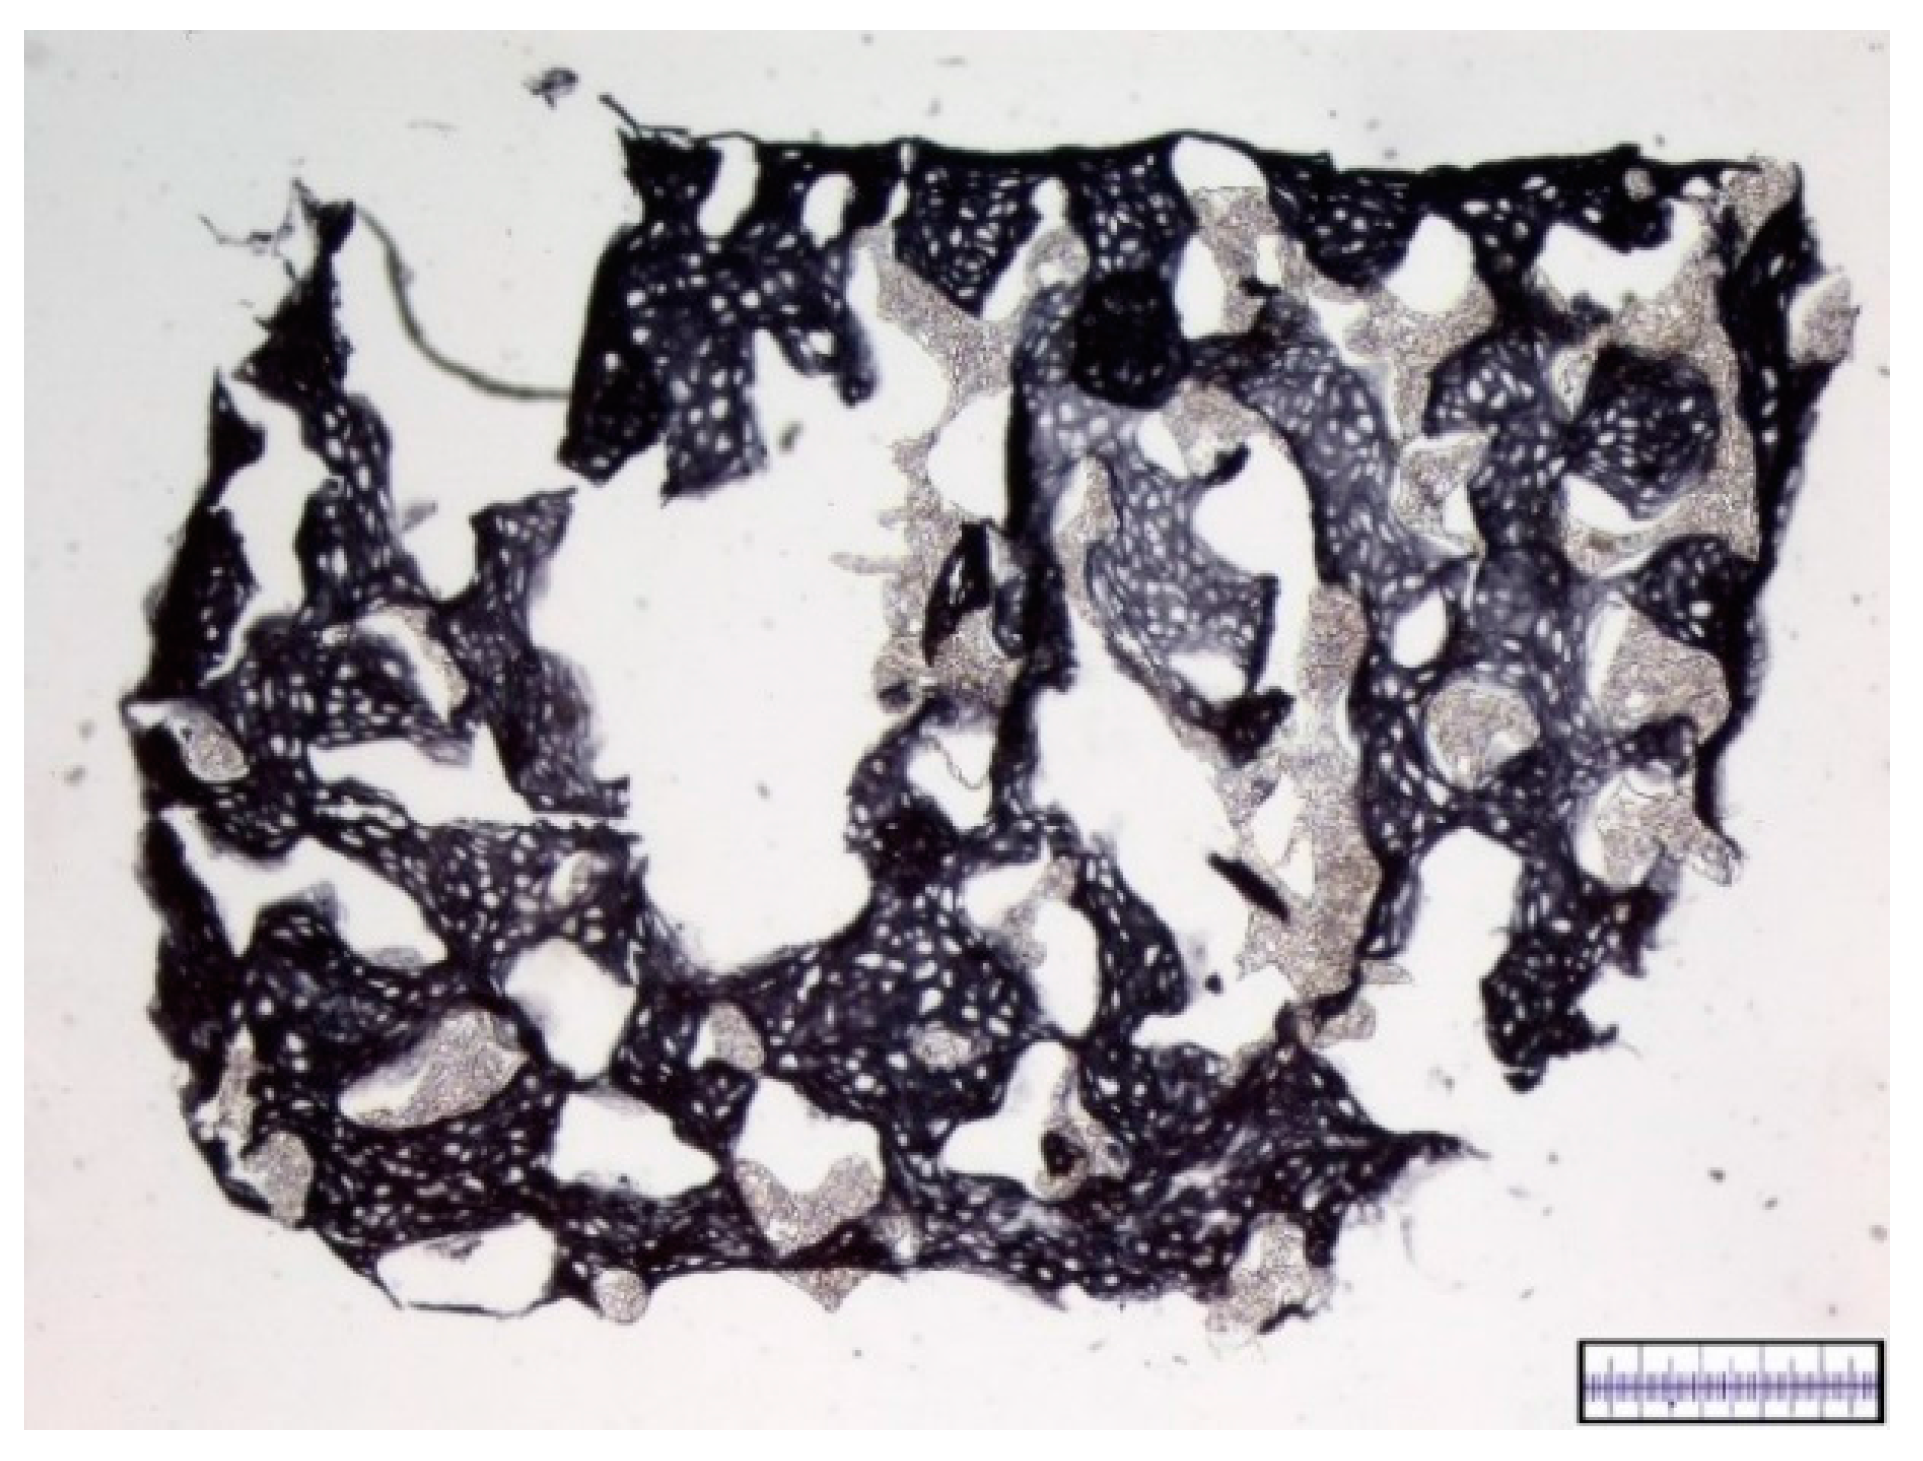

3.1. Macroscopical Assessment of Scaffold Pore Structure

3.2. Interconnectivity of Scaffold Pores